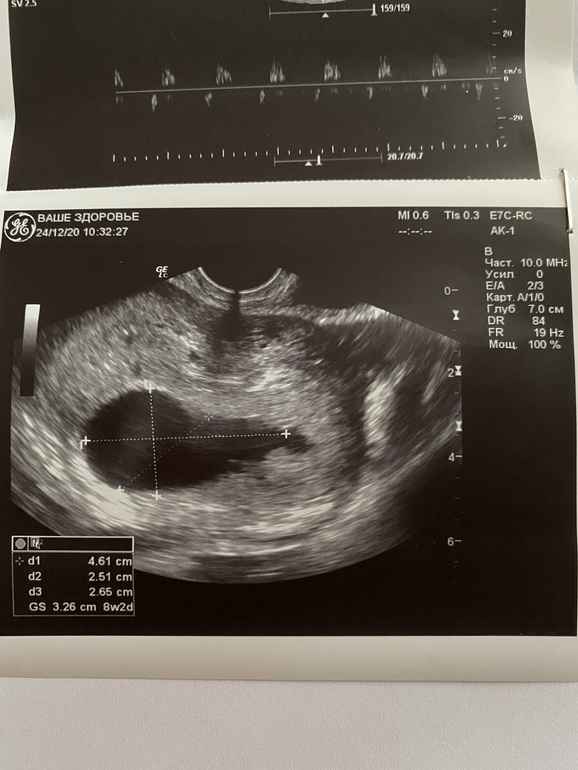

По узи ПЯ (СВД) - 32,6 мм (соотв. сроку 8н 2 дня), а КТР - 4,2 мм (соотв. 6 нед 1 день), сердцебиение определяется

Также врач сказала, что ПЯ неправильной формы, фото прилагаю